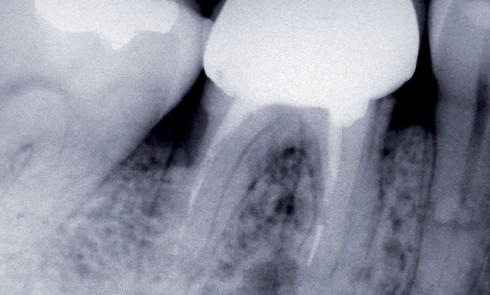

Article réservé à nos abonnés La cavité d’accès a minima

La perte de substance tissulaire de l’organe dentaire, qu’elle soit d’origine carieuse, traumatique ou consécutive à une thérapeutique de préparation...